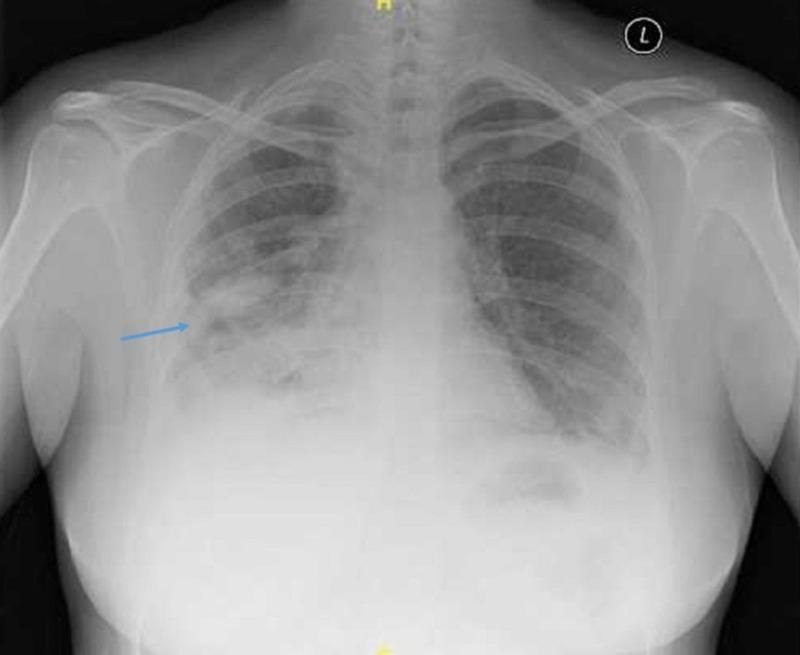

Intracranial tuberculoma is a rare manifestation of tuberculosis involving the central nervous system. The involvement of the ventricular system is extremely uncommon. We describe a young woman with bilateral papilledema secondary to intraventricular tuberculoma with hydrocephalus. She was treated with anti-tuberculosis therapy and intravenous dexamethasone. Her visual acuity deteriorated after one month of treatment. We provide a literature review of this uncommon ocular sequelae.

颅内结核瘤是结核病累及中枢神经系统的一种罕见表现。脑室系统受累极为罕见。我们描述了一名年轻女性,她因脑室结核瘤伴脑积水继发双侧视乳头水肿。她接受了抗结核治疗和静脉注射地塞米松。治疗一个月后她的视力恶化。我们对这种罕见的眼部后遗症进行了文献综述。